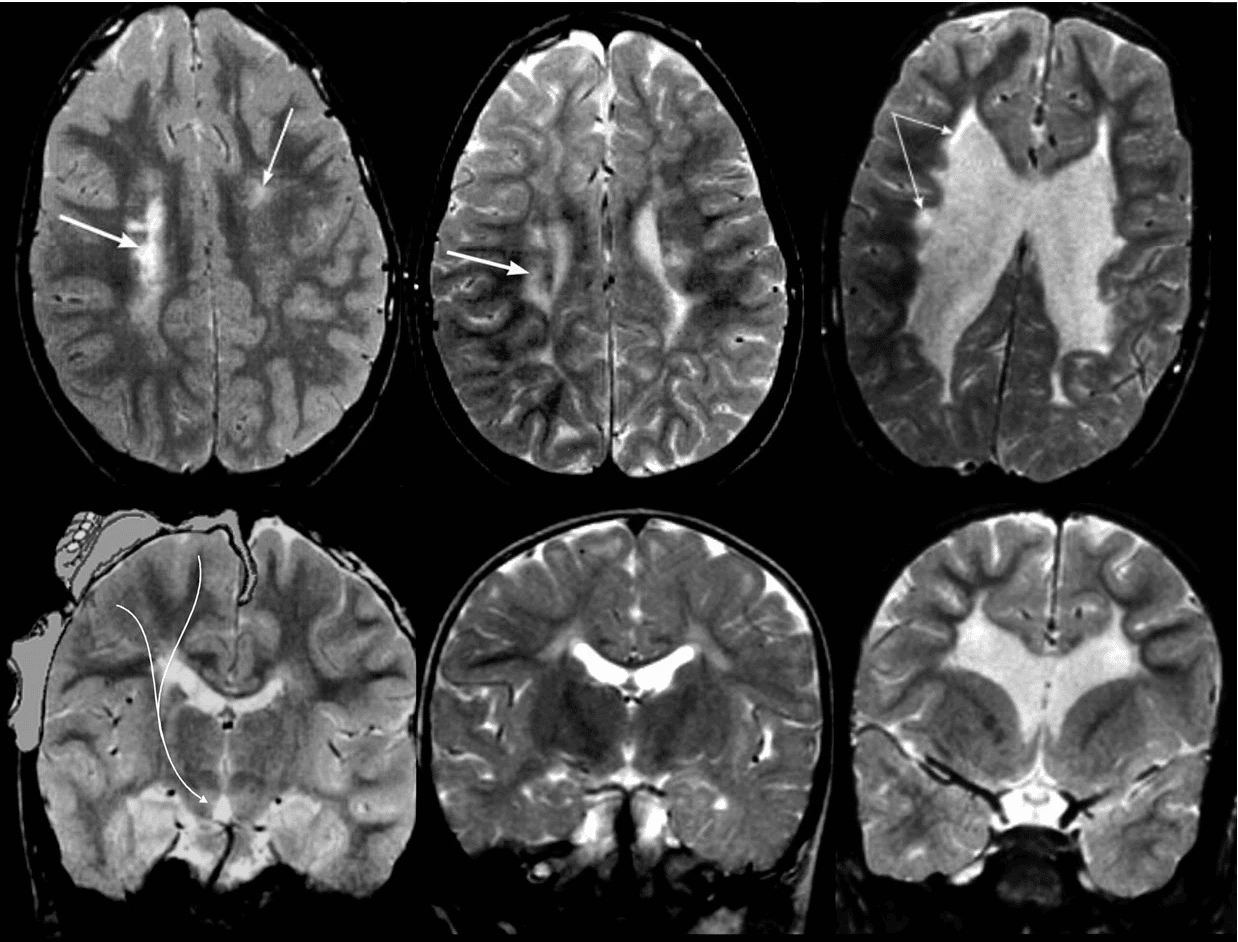

- Cộng hưởng từ (MRI) não: MRI là kĩ thuật sử dụng năng lượng nam châm và sóng radio để tạo ra những hình ảnh của não. Nó có thể nhận diện được những bất thường hay tổn thương trong não.

- CT scan não: xét nghiệm này tạo ra những hình ảnh cắt ngang, rõ nét về não. Nó cũng phát hiện những tổn thương trong não.